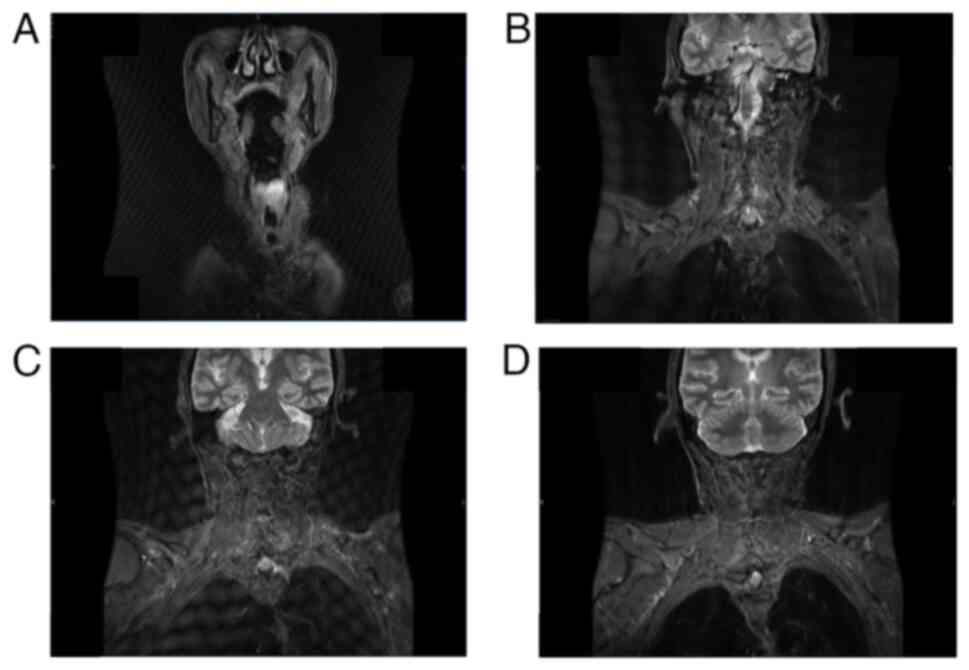

The significant increase in tumor size within <1 month between both laryngoscopic examinations aligned with the findings from previous imaging studies and further underscored the characteristic features of sarcomatoid carcinoma of the larynx, namely high malignancy and rapid progression. Then, at 5 days prior surgery the patient was subjected to neck magnetic resonance imaging scan with both plain and enhanced scans. The results showed that the tumor size was ~2.8×1.9 cm2 (Fig. 3A-D), which signified a significant increase compared with the spiral CT results obtained 1 month prior, thereby highlighting the rapid tumor progression rate. In addition, immunohistochemical pathological analysis of preoperative outpatient tumor biopsy sections taken 1 month prior to surgery under local anesthesia was performed using rapid paraffin-embedded tissue sections [Fig. 4A, Image 1 of the preoperative biopsy paraffin section indicating nuclear atypia and typical spindle-shaped cells; Fig. 4B, Image 2 of the preoperative biopsy immunohistochemistry showing positivity for cytokeratin (CK) and vimentin]. Eventually, based on its morphology and immunophenotyping, the patient was diagnosed with laryngeal sarcomatoid carcinoma. The laryngeal tumor was classified as T2N0M0, according to the established criteria of the TNM staging system (19).

Figure 3.

Coronal contrast-enhanced magnetic resonance images of the larynx 5 days prior surgery. (A) Coronal image 1. (B) Coronal image 2. (C) Coronal image 3. (D) Coronal image 4.